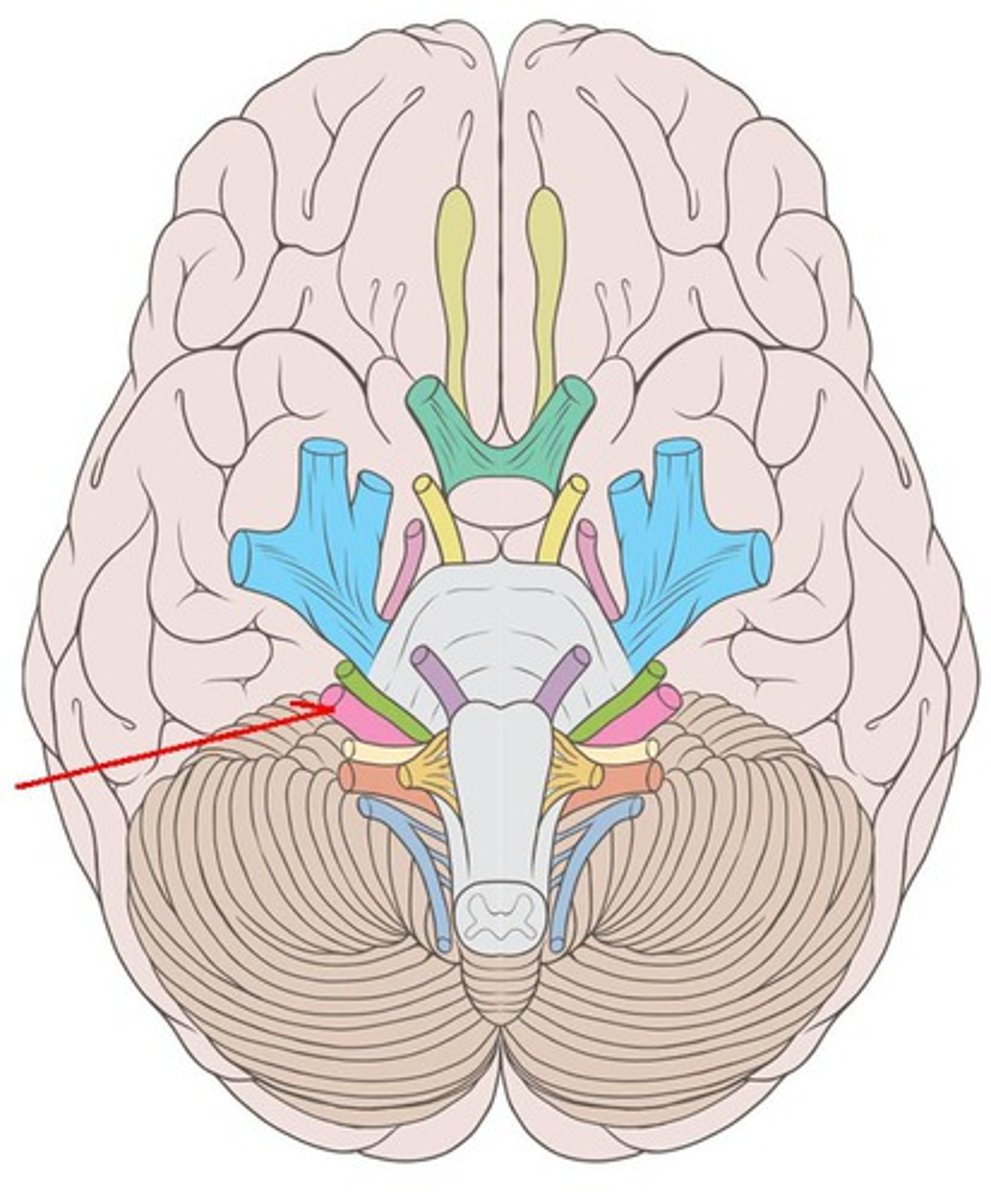

Brain Anatomy

71 Terms

branches of olfactory nerve (cranial nerve I)

olfactory bulbs

olfactory tracts

optic nerves (cranial nerve II)

optic chiasma

optic tracts

CNIV (trochlear nerve)

CNVI (abducens nerve)

CNIII (oculomotor nerve)

CNVIII (vestibulocochlear) (acoustic nerve)

CNX (vagus nerve)